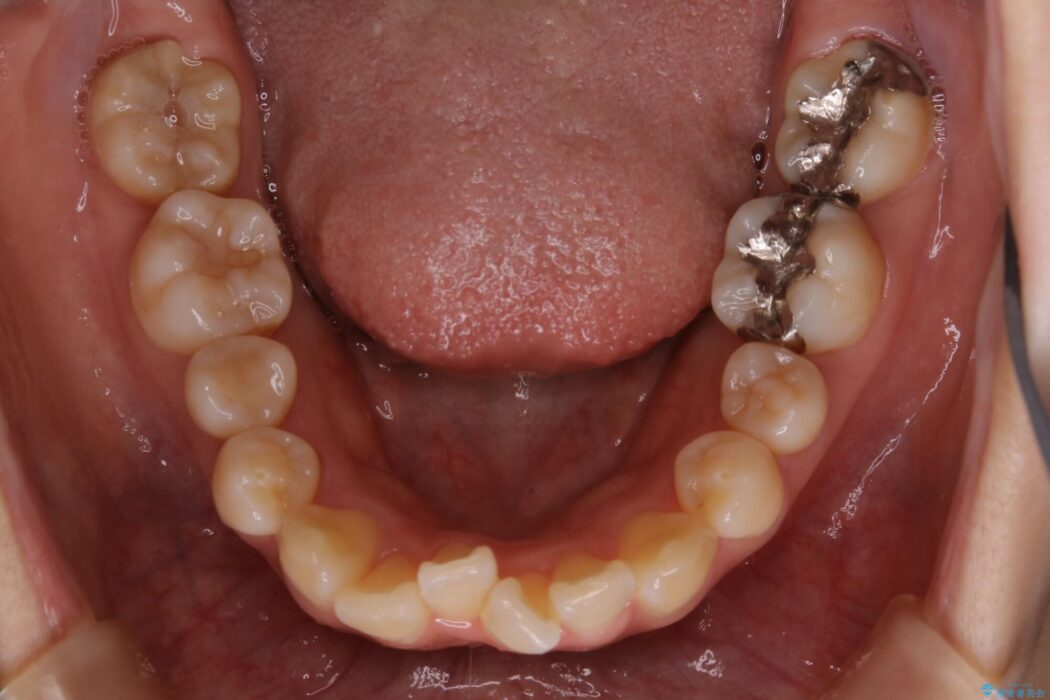

治療後について

患者様の意識も高く、しっかりとマウスピースを装着していただけたこともあり満足できる仕上がりとなりました。

本症例では最大量の移動もあり治療期間が掛かってしまいましたが、非抜歯でマウスピース矯正をしたいというご希望に応えることができました。

非抜歯での矯正治療

マウスピースにマイクロインプラントという補助装置を併用することで抜歯をせずとも歯列を整えるスペースを確保することができます。奥歯から順に移動させていくので前歯に変化が出るまでには時間がかかってしまいますが、健康な歯を抜歯することなく理想的な歯並びを手に入れることができます。